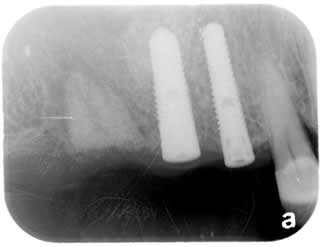

Implant Crowns:

April 2009

Splinted Crowns are cemented onto the two implants.

Imlants crowns are usually splinted together to enhance lateral oblique biting force.